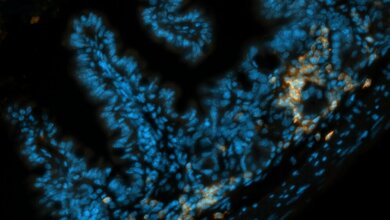

Um zu überprüfen, ob das neu gewonnene Wissen in der Praxis angewendet werden könnte, testeten die Forscher zwei Wirkstoffe, die den Mechanismus an zwei verschiedenen Stellen unterbrechen: Im Versuchsmodell konnten sie zeigen, dass sowohl der KRAS Inhibitor Deltarasin** als auch ein Antiköper gegen den von den Krebszellen ausgesandten Botenstoff dem Pleuraerguss entgegenwirkten.

Bereits 2015 hatte ein Team um Stathopoulos herausgefunden, dass bei Lungenkrebs sich Mastzellen in der Pleurahöhle ansammeln und dort einen Pleuraerguss erzeugen. Erste Versuche mit dem Hemmstoff Imatinib zeigte im präklinischen Modell einen verminderten Pleuraerguss und weniger Mastzellen.